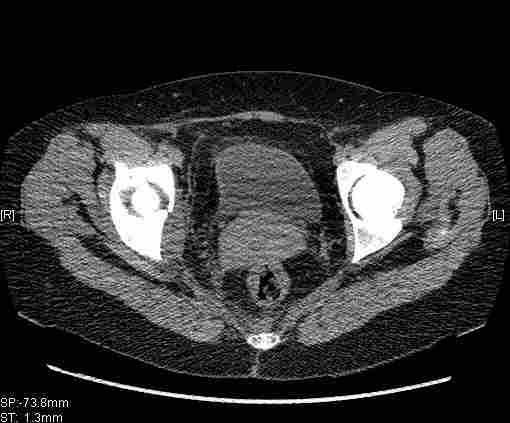

[Ortho] [1/2] Re: Т-образный перелом вертлужной впадины

Удалось сегодня вывести пациентку в соседнюю больницу, где есть кт.

Срезы сделаны  только горизонтальные.